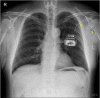

Peripheral nerve stimulation (PNS) is a useful treatment for chronic pain, but it can cause damage depending on its application site. Here, we describe the case of a 54-year-old man who underwent PNS for brachial plexopathy in 2015. One lead was implanted on the left medial cord to stimulate the medial antebrachial cutaneous nerve, and the other was implanted on the radial nerve to stimulate the posterior antebrachial cutaneous nerve. Both leads were inserted near the shoulder joint but did not cross it. Before PNS, the patient did not move his shoulder and elbow because of severe pain, but the treatment greatly alleviated this pain. Twenty months after the operation, both leads were fractured, and the severe pain returned. Repetitive motion near the joint was closely related to the lead fractures. In conclusion, large joints as the insertion sites of PNS leads should be avoided to prevent lead fractures.